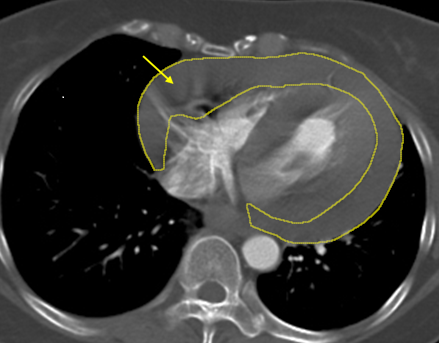

【記者葉柏成/新北報導】46 歲陳姓女子日前騎機車返家途中突感頭暈、意識不穩,機車失控摔倒,經路人協助緊急送抵 土城長庚醫院 急診時已陷入休克狀態。急診醫療團隊迅速啟動重症評估與影像檢查,電腦斷層顯示患者心臟外層已迅速累積大量心包積血,並高度懷疑合併外傷引發的 「升主動脈剝離」——一種死亡率極高、分秒必爭的致命急症。醫院立即展開跨科整合搶救機制,在關鍵 72 小時內完成三次重大手術,將患者從生死邊緣拉回,目前已順利康復出院。

胸腔及心臟血管外科主治醫師鄭元熙指出,心包積血是指血液在極短時間大量堆積於心臟外層的心包腔內,造成心臟受壓,無法正常擴張與跳動,血壓會迅速下降,甚至在數分鐘內導致心跳停止,是典型的致命急症;而升主動脈為全身最粗大的主動脈,一旦發生剝離或破裂,出血速度之快猶如水管爆裂,臨床上常見患者尚未送醫前即已失去生命跡象。

陳小姐回憶,自己過去長期有反覆頭暈困擾,曾因突發頭暈騎腳踏車摔倒,但症狀短暫且未就醫檢查。此次意識喪失送醫後,影像檢查確診為大量心包積血及疑似主動脈剝離後,醫療團隊第一時間成立跨科搶救小組,由心臟外科緊急執行「劍突下心包開窗術」,迅速解除心臟壓迫並穩定循環;隨後無縫接軌由血管外科進行高難度的「升主動脈置換術」,以人工血管重建破裂主動脈。整體手術歷時甚長,醫療團隊全程與時間競速,並於術後陸續完成止血、調整及胸骨固定等關鍵處置。